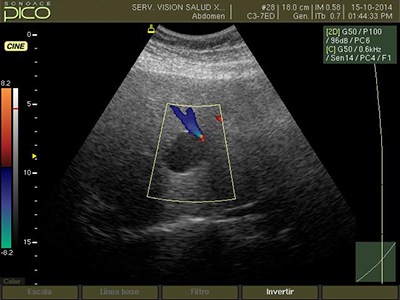

El ultrasonido o eco abdominal es un estudio diagnóstico solicitado frecuentemente por especialistas de casi todas las áreas médicas para descartar o confirmar diversos diagnósticos de enfermedades intraabdominales; se trata de un estudio no invasivo, relativamente barato y fácil de hacer sin embargo prestar atención a los pequeños detalles es lo que diferencia un eco abdominal de un excelente eco abdominal.

Otra de las razones por las que se debe estar en ayuno antes de realizar un eco abdominal es para permitir que la vesícula biliar se encuentre llena de bilis; la vesícula funciona como un reservorio en el cual se acumula la bilis esperando a ser usada cuando se necesite, al iniciarse el proceso de ingesta de alimentos un conjunto de señales nerviosas y bioquímicas estimulan la contracción de la vesícula biliar para que libere su contenido hacia la vía digestiva; si bien esto es óptimo para el proceso digestivo resulta inconveniente cuando se realizará un eco abominal ya que una vesícula vacía estará colapsada, con pliegues en su mucosa y muchas veces retraída hasta lo más profundo del lecho vesicular, en estas condiciones resulta casi imposible diferenciar un pólipo de un cálculo en la vesícula así mismo piedras muy pequeñas podrían quedar ocultas en los pliegues lo mismo que el barro biliar; resulta pues imposible realizar un diagnóstico preciso de pat0logía de la vesícula biliar si el paciente no ha guardado ayuno antes del eco permitiendo así que la vesícula biliar se encuentre a su máxima capacidad.